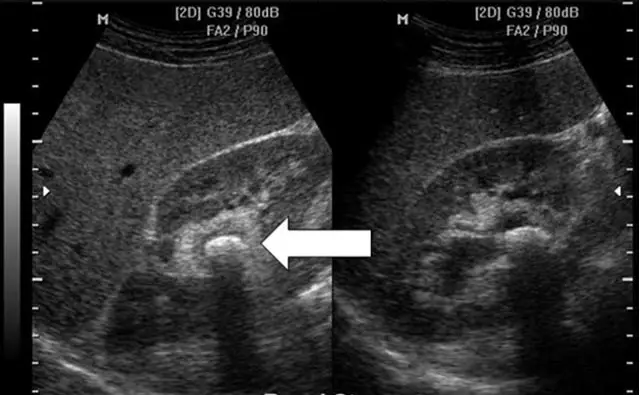

下圖為腎臟超音波縱向影像,箭號所指的是:

題目提供了兩張腎臟縱切面超音波影像(同一部位的不同切面或參數)。

- 正常結構:影像中可見腎臟實質(較低回音的皮質區)以及中央高回音的腎竇(renal sinus)區域。

- 異常病灶:在白色粗箭頭所指之處,位於腎竇/腎盂(收集系統)區域內,可見一個極高回音(強烈反白亮點,hyperechoic focus)的弧狀結構。

- 關鍵假影(Artifact):在此高回音病灶的正後方(影像下方方向),伴隨著一道明顯的黑色帶狀陰影,稱為**「後方音響陰影(posterior acoustic shadowing)」**。這是由於超音波遇到高密度、高反射的鈣化物質時,聲波被強烈反射與吸收,無法穿透而在其後方形成的典型物理現象。